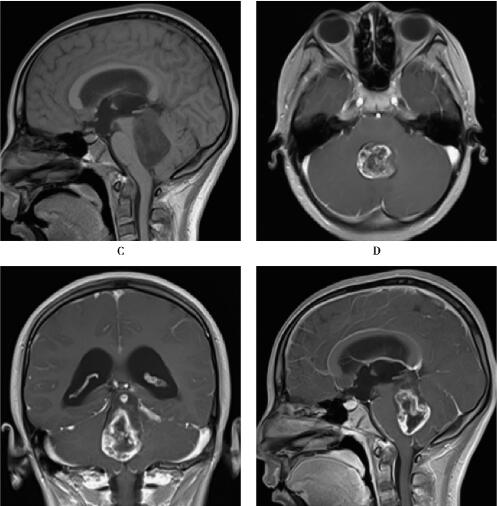

扫描应用3.0T超导型MRI仪(Siemens Magnetom Trio Tim),8通道头部线圈,患者取仰卧位,头先进。应用体轴横断位T1WI(TR/TE=500ms/8.9ms,5mm层厚)、T2WI(TR/TE=4500ms/87ms,5mm层厚)。应用钆喷酸葡胺(Gd-DTPA)注射液20ml,经手背静脉以高压注射器4ml/s流率注入,随之以0.9%生理盐水20ml冲入,4分钟后扫描。MRI表现见图1。

图1 第四脑室毛细胞星形细胞瘤:MRI平扫第四脑室内类圆形异常信号,T2WI呈高信号,T1WI呈低信号,增强后强化明显,呈花环样强化